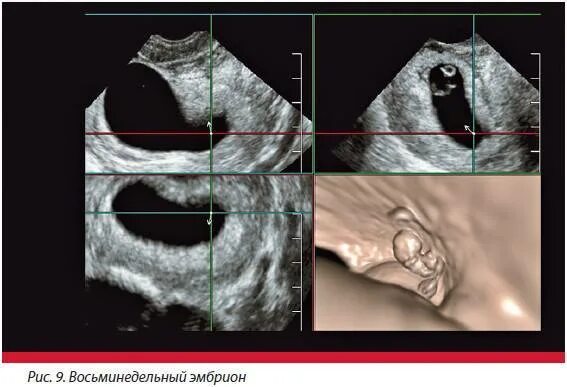

Плодном яйце не визуализируется эмбрион